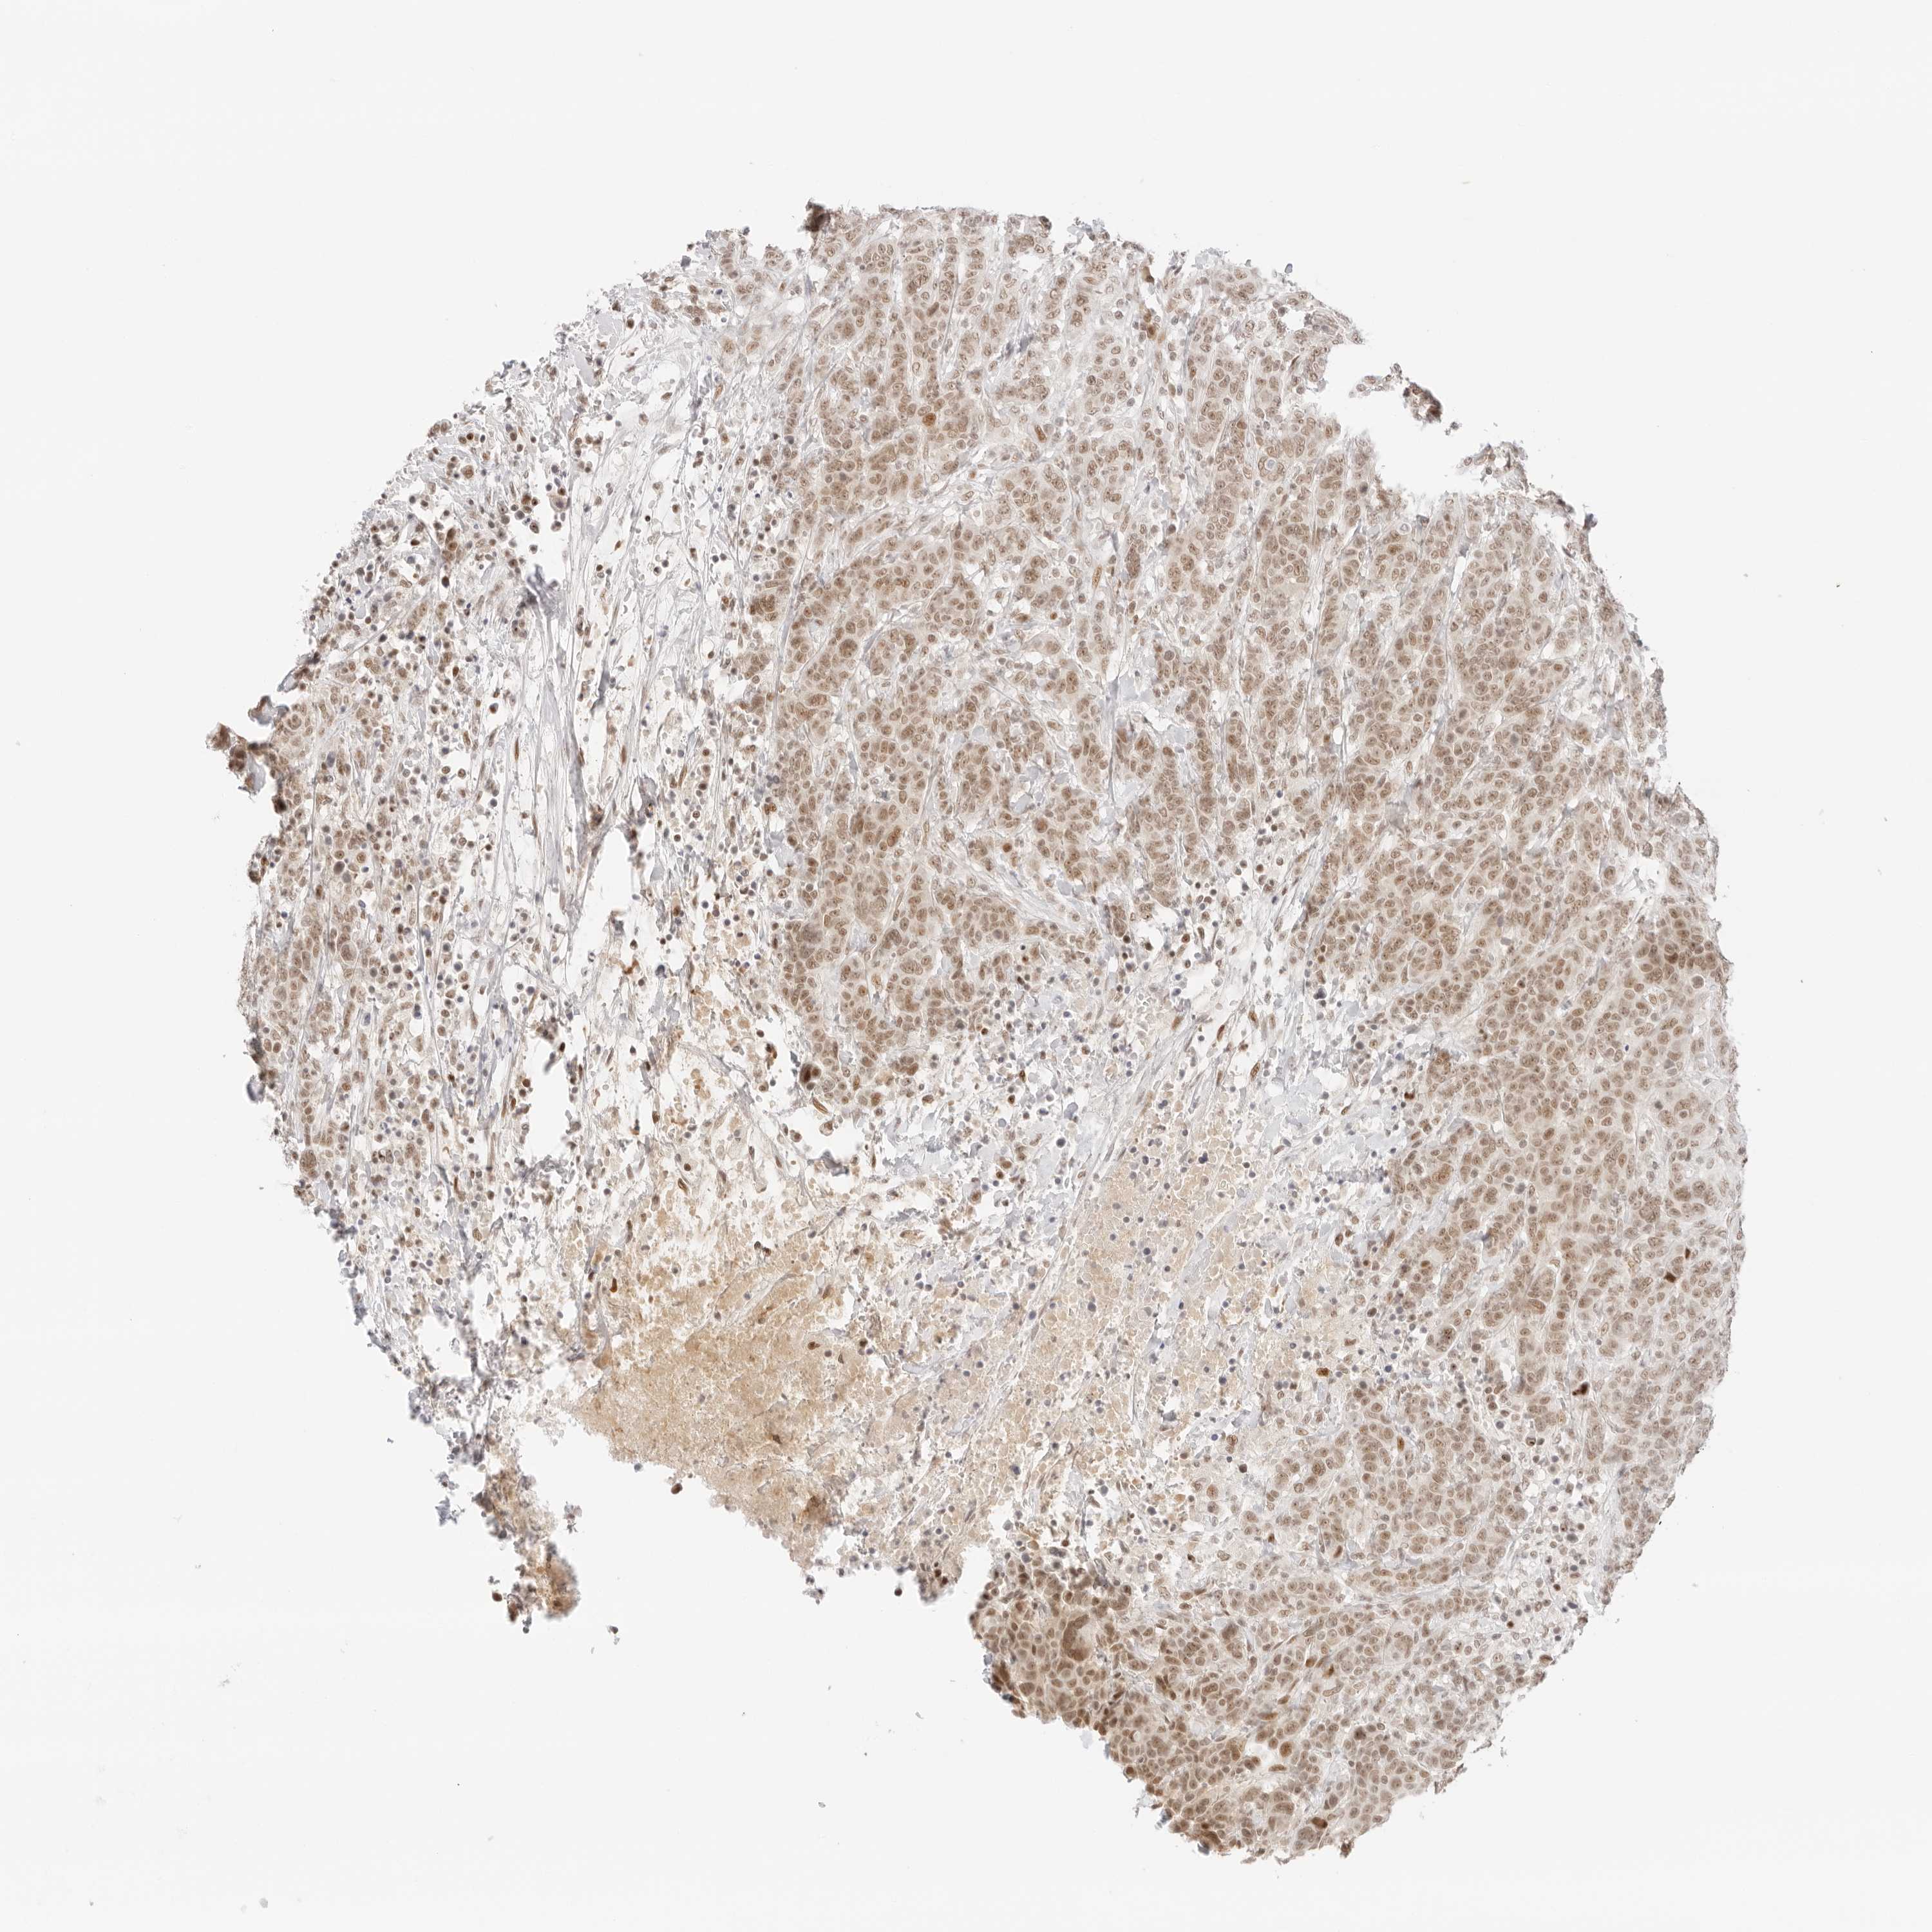

BRCA TCGA BRCA VALIDATION PROTEIN EXPRESSION